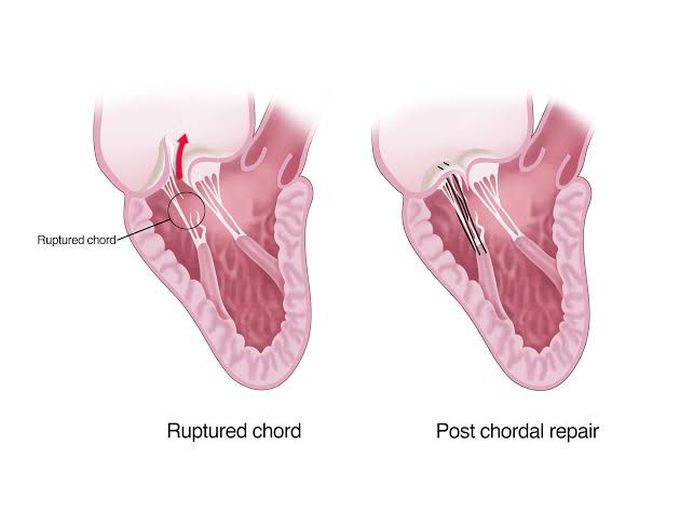

CLINICAL CASE OF ACUTE CHORD RUPTURE OF THE MITRAL VALVE POSTERIOR

rrmedicine.ru

rrmedicine.ru

rupture leaflet mitral posterior figure valve patient chord morbidities clinical acute older case hg pulmonary hypertension mm

Mitral Valve Repair With A Device For Artificial Chordal Implantation

www.jtcvsopen.org

www.jtcvsopen.org

Clinical Case Of Acute Chord Rupture Of The Mitral Valve Posterior

www.researchgate.net

www.researchgate.net

mitral leaflet rupture valve posterior chordae clinical acute morbidities patient chord older case